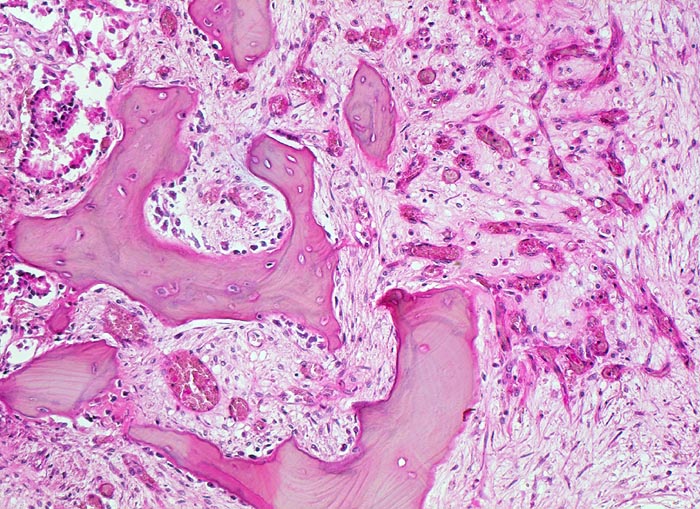

Da Adenokarzinome neben der Prostata in fast allen Organen vorkommenen, ist die Differentialdiagnose im HE Schnitt bei Nachweis einer Knochenmetastase eines Adenokarzinoms sehr breit. Die immunhistochemische Positivität der Tumorzellen für prostataspezifisches Antigen (PSA) spricht für eine Primärtumorherkunft aus der Prostata. Prostatakarzinome bilden typischerweise osteoplastische Knochenmetastasen. Die Knochenbildung erfolgt via Cytokine und Wachstumsfaktoren, die von den Tumorzellen gebildet werden (z.B. TGF-beta), durch Stimulation der Osteoblasten, wahrscheinlich bei gleichzeitiger lokaler Reduktion der Osteoklastenaktivität (RANK/RANKL/OPG-System). Die Stimulation von Osteoblasten führt zu einer vermehrten appositionellen Osteoidneubildung entlang vorhandener Trabekel mit nachfolgender Mineralisierung. Durch fortgeschrittene Knochenneubildung kommt es zu einer vollständigen Ummauerung grösserer Tumorareale, welche durch die verminderte Blutzufuhr nekrotisch werden. Vielfach lassen sich histologisch osteoplastische und osteolytische Anteile nachweisen. Immunhistochemisch lässt sich in den Metastasen oft Prostata spezifisches Antigen nachweisen (> 5342).

Morphologische Merkmale:

• Fehlen von blutbildendem Knochenmark.

• Infiltration des Knochemarks durch kleine dichtgepackte, kribriforme Strukturen ausbildende Karzinomdrüsen.

• Osteplastische Metastase: Faserknochenneubildung zwischen vorbestehenden Trabekeln.

• Anhand der Histologie kann lediglich die Diagnose einer Metastase eines Adenokarzinoms gestellt werden. Kleine, solide Verbände bildende Tumordrüsen und grosse Nukleolen sind typisch für ein Prostatakarzinom. Die Diagnose muss aber durch den Vergleich mit der Morphologie des Primärtumors oder eine Immunhistochemische Untersuchung (PSA, PSAP) bestätigt werden.